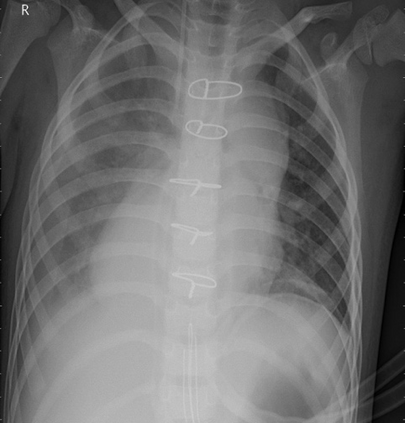

Pneumonia remains a leading cause of morbidity and mortality worldwide. Chest X-ray (CXR) imaging is a fundamental diagnostic tool, but traditional analysis relies on time-intensive expert evaluation. Recently, deep learning has shown immense potential for automating pneumonia detection from CXRs. This paper explores applying neural networks to improve CXR-based pneumonia diagnosis. We developed a novel model fusing Convolution Neural networks (CNN) and Vision Transformer networks via model-level ensembling. Our fusion architecture combines a ResNet34 variant and a Multi-Axis Vision Transformer small model. Both base models are initialized with ImageNet pre-trained weights. The output layers are removed, and features are combined using a flattening layer before final classification. Experiments used the Kaggle pediatric pneumonia dataset containing 1,341 normal and 3,875 pneumonia CXR images. We compared our model against standalone ResNet34, Vision Transformer, and Swin Transformer Tiny baseline models using identical training procedures. Extensive data augmentation, Adam optimization, learning rate warmup, and decay were employed. The fusion model achieved a state-of-the-art accuracy of 94.87%, surpassing the baselines. We also attained excellent sensitivity, specificity, kappa score, and positive predictive value. Confusion matrix analysis confirms fewer misclassifications. The ResNet34 and Vision Transformer combination enables jointly learning robust features from CNNs and Transformer paradigms. This model-level ensemble technique effectively integrates their complementary strengths for enhanced pneumonia classification.